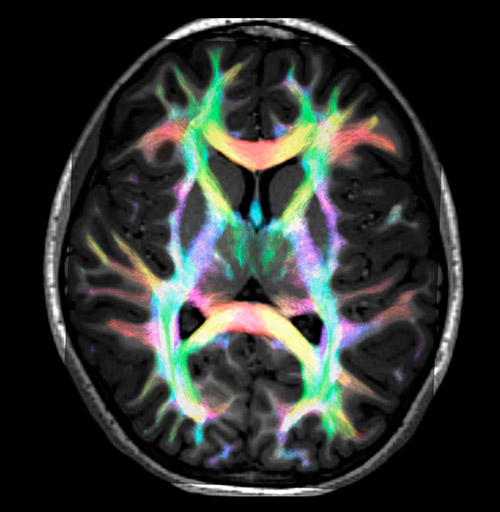

Fiber tractography of the corticospinal tract with seed region of the posterior limb of the internal capsule. Different processing based on the same data.

All images were created from the same acquisition in a child using Ingenia 3.0T CX and 32-channel dS Head coil. Diffusion data was acquired at b-values 0, 500, 1000, 2000, 3000. The use of high b-values (3000 s/mm2) effectively suppresses extra-axonal water signal and provides high angular resolution.

Super-resolution directionally encoded color track-density imaging overlaid on T1-weighted structural MRI.